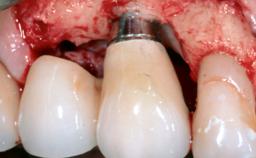

Surgical Management of Peri-Implantitis: Reconstructive Surgical Treatment with Three-Year Follow-up After Treatment

Despite anti-infective surgical treatment, some patients may experience recurrent infection and progressive bone loss requiring additional treatment. Removal of Implant Due to Recurrent Infection describes a conservative approach using an implant retrieval tool without the need for excessive bone removal or use of a trephine.

A 70-year-old female patient was referred by her general dentist to the periodontist for assessment and management of an infection associated with implant 36. The general dentist had noted suppuration on probing during examination.